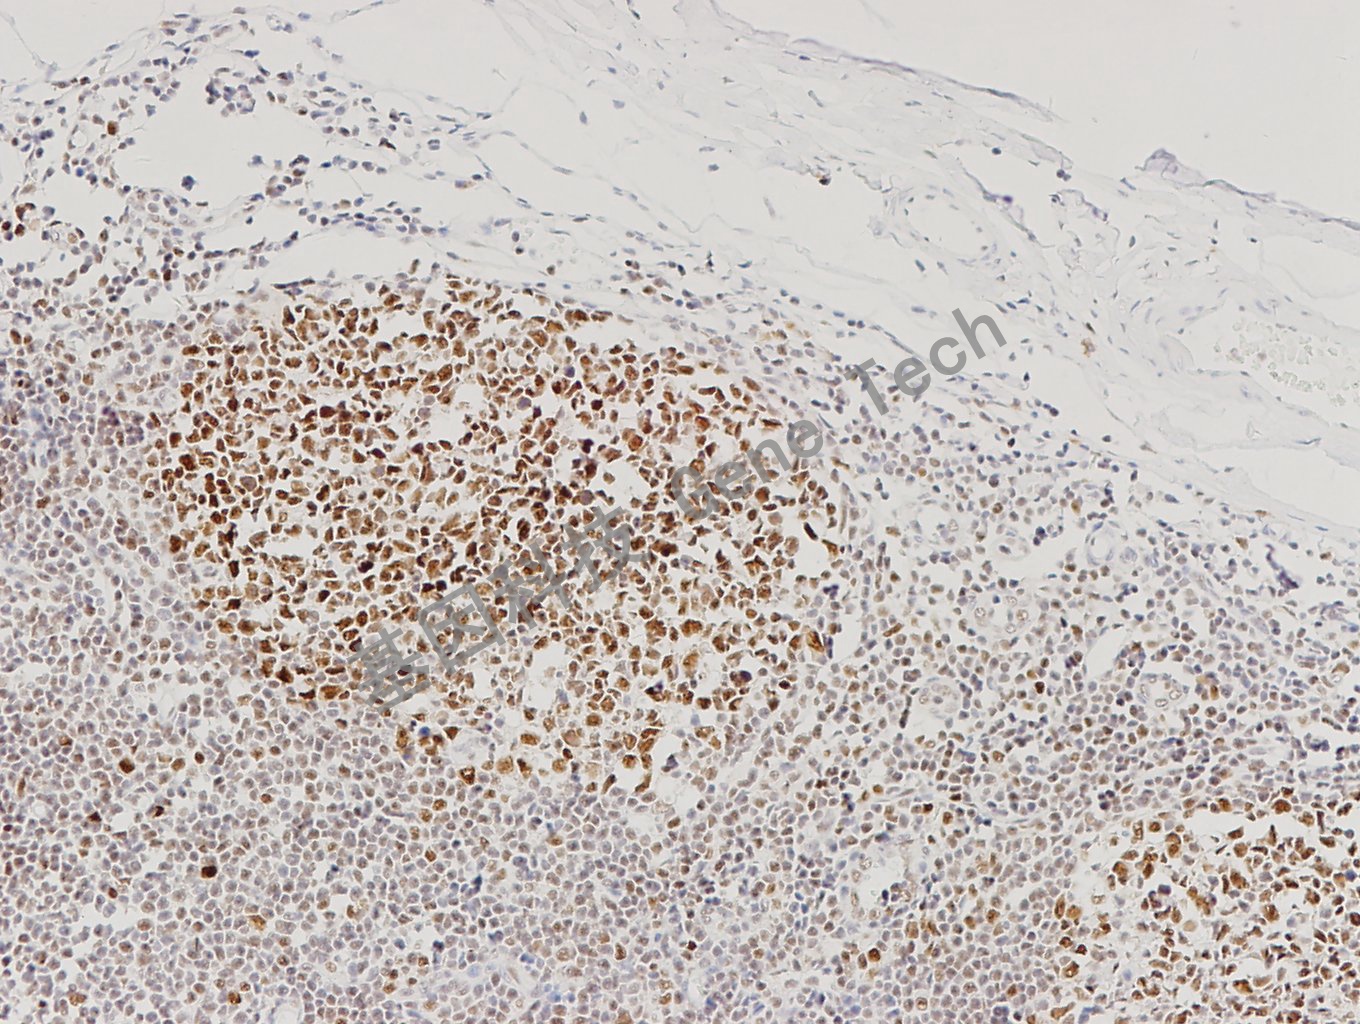

扁桃体石蜡切片,用 MLH1(GT2304)染色,细胞核阳性,DAB 显色。